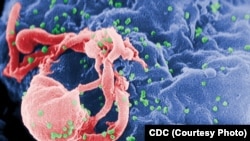

HIV adalah singkatan dari human immunodeficiency virus.

Berdasarkan keterangan yang dimuat di situs Pusat Pengawasan dan Pencegahan Penyakit Amerika (CDC), HIV disebut berasal dari salah satu jenis Simpanse di Afrika Tengah.

Ilmuwan meyakini, “jenis HIV yang diidap simpanse itu menginfeksi manusia dan bermutasi, karena manusia memburu dan memakan hewan itu. Kemungkinan besar kita terinfeksi karena kontak dengan darah simpanse yang mengidap virus.”

Dan HIV menyerang sistem imun, terutama sel CD4. Sel ini berfungsi membantu sistem imun melawan penyakit.

Jika tidak diobati, maka HIV akan terus membunuh sel CD4, membuat tubuh penderitanya gampang terinfeksi berbagai macam penyakit.